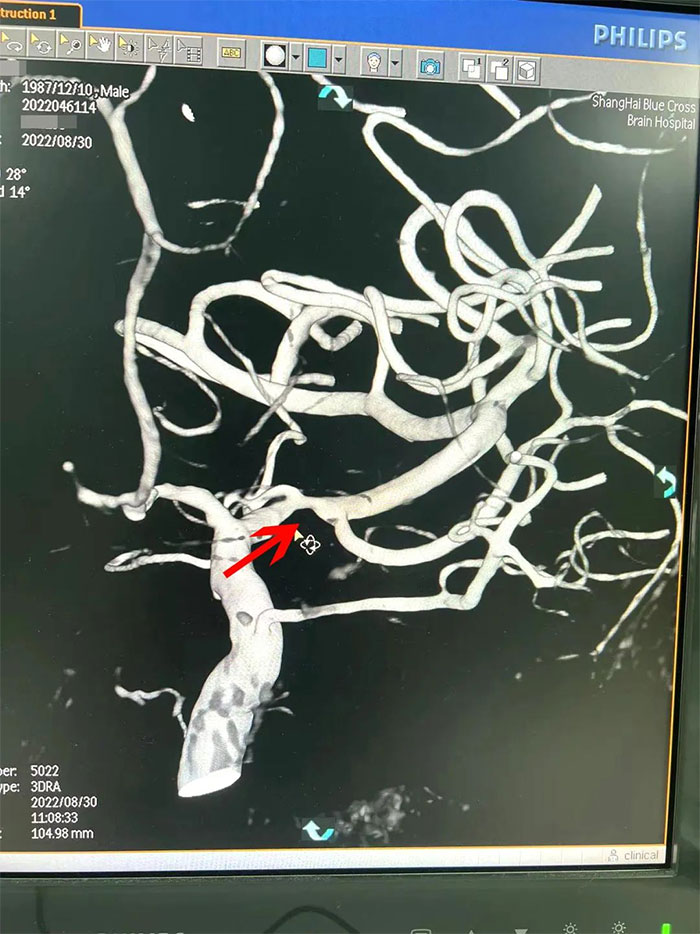

在检查中发现,周先生右侧大脑中动脉M1段闭塞,可见烟雾状异常血管网生成;左侧大脑中动脉M1段重度狭窄(约70%)。符合烟雾病的典型影像学特征。

▲ 检查发现烟雾状异常血管网

▲右侧大脑中动脉M1段闭塞,左侧重度狭窄

烟雾病又名Moyamoya病,脑底异常血管网,是一组以Willis环双侧主要分支血管(颈内动脉虹吸段及大脑前、中动脉,有时也包括大脑后动脉)起始部慢性进行性狭窄或闭塞,继发出现侧支异常的小血管网为特点的脑血管病。因脑血管造影时,呈现许多密集成堆的小血管影,似吸烟时吐出的烟雾而得名。